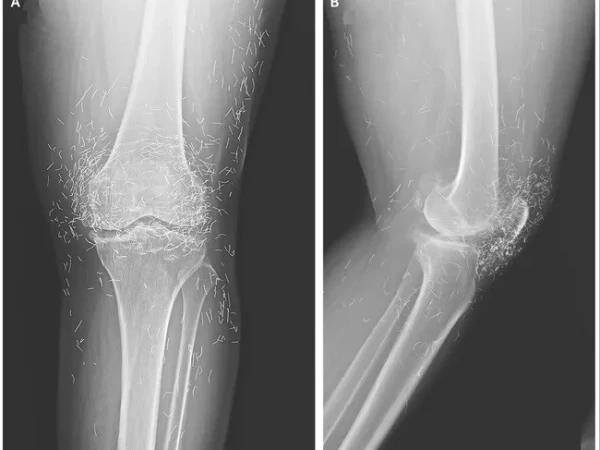

مذکورہ بالا تصویر ایک 65 سالہ خاتون کے گھُٹنے کے ایکسرے کی ہے جس میں دیکھا جا سکتا ہے کہ گھٹنے کے گرد سینکڑوں چھوٹے سونے کے تارموجود ہیں۔

بعد ازاں خواتین کے گھٹنے کا ایکس رے کیا گیا اور جو چیز سامنے آئی، وہ گھٹنے کے اندر سونے کے انتہائی باریک تار تھے۔ دراصل یہ تار اکیوپنکچر کے دوران باقاعدہ طریقے سے اندر چھوڑ دیے گئے تھے تاکہ جسمانی تحریکی (stimulation) اثر برقرار رہے۔